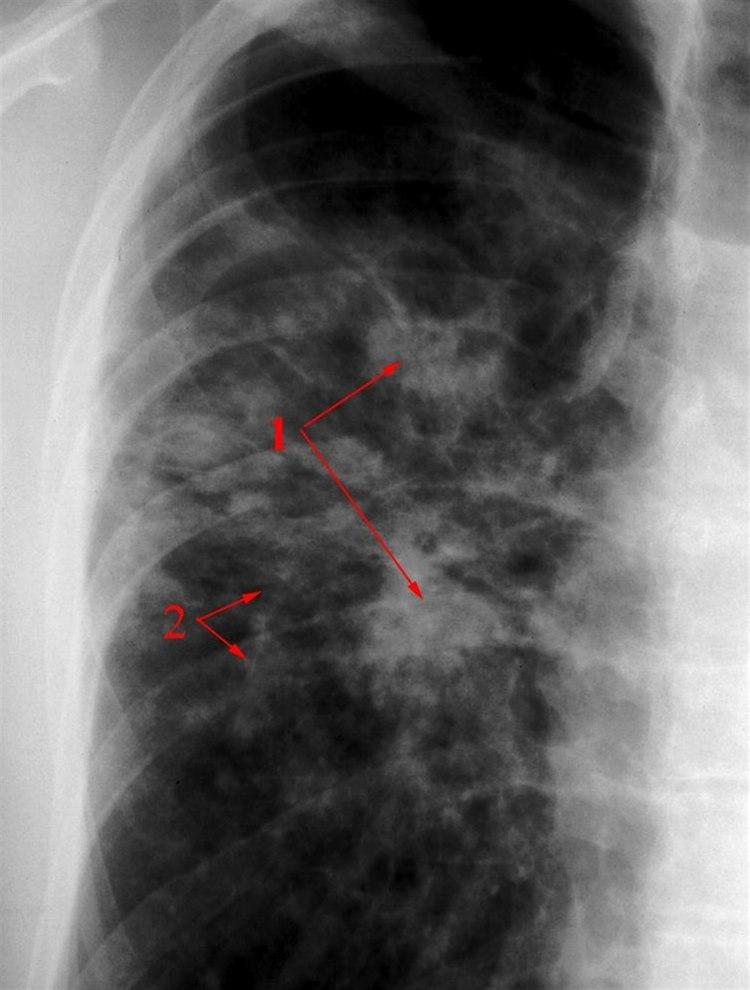

Sarkoidose i lungerSymptomene kan gi mistanke, men oftest vil det være røntgenbilder som viser de typiske forandringene i lungene (se bilde). For å kunne stille en sikker diagnose er det likevel nødvendig med mikroskopisk undersøkelse av en vevsprøve fra lungene, noe som vanligvis blir tatt i forbindelse med bronkoskopi. På bakgrunn av røntgenbildene kan sarkoidose inndeles i ulike stadier fra stadium I (minst uttalt) til stadium IV (mest uttalt).